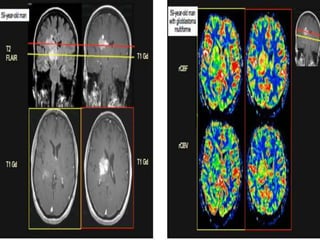

45-year-old woman presenting with

right hemiparesis and headache. A)

Axial T1-weighted image (TR 450, TE

20, NEX 1, 0.2 mmol/Kg gadolinium

injected at 5 cc/s) shows an

enhancing lesion in the right pons,

midbrain, and thalamus. B) CBV map

shows elevated blood volume within

the lesion, consistent with high-grade

neoplasm (perfusion raw data

obtained at TR 500, TE 65, 5-mm

thick, 6-mm skip, 0.2 mmol/Kg

gadolinium injected at 5 cc/s). C) MR

spectroscopy shows a high choline to

creatine ratio and a decrease in N-acetyl

aspartate, also consistent with

high-grade tumor (single voxel

technique, TR 1500, TE 144). D) FDG-PET

shows foci of high glucose

metabolism within the lesion, also

consistent with high-grade tumor.